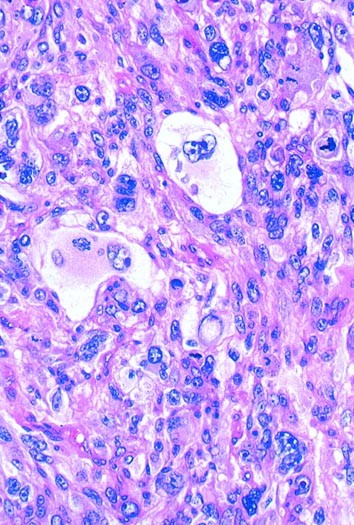

A pleomorphic sarcoma can be defined simplistically as one in which the cells display marked atypia (Fig. 8). It is not altogether synonymous with undifferentiated because many pleomorphic sarcomas display evidence of differentiation. As a group, pleomorphic sarcomas occur in adults and, therefore, contrast with poorly differentiated sarcomas occurring in children, which are usually round cell lesions. Some pleomorphic sarcomas arise de novo, whereas others evolve through the process of dedifferentiation (e.g., dedifferentiated liposarcoma; 2, 3) through a series of mutagenic events not well understood. Although many types of sarcoma occasionally assume a pleomorphic appearance, there are some that consistently or even definitionally have a pleomorphic appearance. These include malignant fibrous histiocytoma (4, 5), dedifferentiated (3) and pleomorphic liposarcoma (6, 7, 8) (Fig. 9), pleomorphic rhabdomyosarcoma (9, 10, 11) (Fig. 9), and pleomorphic leiomyosarcoma (11, 12). For purposes of this lecture, we will consider all pleomorphic sarcomas as high grade, although there are some exceptions.

Concurrent with the plethora of clinical studies, pathologists continued to investigate the lineage of this tumor. On the basis of a large body of literature, it gradually became clear that the cells of the malignant fibrous histiocytoma possessed neither the ultrastructural nor immunophenotypic profile of the histiocyte but rather were more closely related to primitive mesenchymal cells or fibroblasts (33, 34, 35, 36). By immunohistochemistry, they lacked the usual enzymes (e.g., lysozyme; 34, 35) and surface markers (CD45, CD14,CD15; 35) associated with histiocytes and possessed, according to electron microscopy, prominent branching endoplasmic reticulum similar to fibroblasts (36; Fig. 18). Moreover, features often attributable to histiocytes, such as prominent primary and secondary lysosomes, which were observed in some cells in malignant fibrous histiocytoma, were easily explained by the phagocytic properties often acquired by neoplastic cells. However, study of the intermediate filaments in these lesions disclosed the unexpected presence of keratin, desmin, and even neural filaments (37, 38), raising the question of whether these unusual profiles reflected aberrant expression or a subtle form of differentiation not previously appreciated.